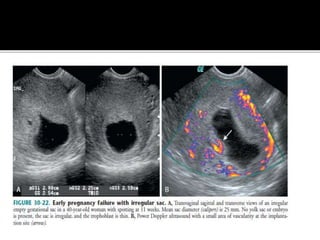

 Irregular Sac.

 Hyperechoic collection

within the sac.

 A subchorionic haemorrhage is often seen,

but unless large does not carry a poor

prognosis.

 Features which do predict poor outcome

include:

• Fetal bradycardia : < 80 - 90 bpm

• Small or Irregular Gestational Sac : MSD -

CRL < 5 mm

• Large Subchorionic Haemorrhage

 One important difference is to be deduced

between an actual irregular sac & a sac which

appears irregular due to Braxton-Hick’s

contractions.

 The former one, will not change its shape

to become normal with time.